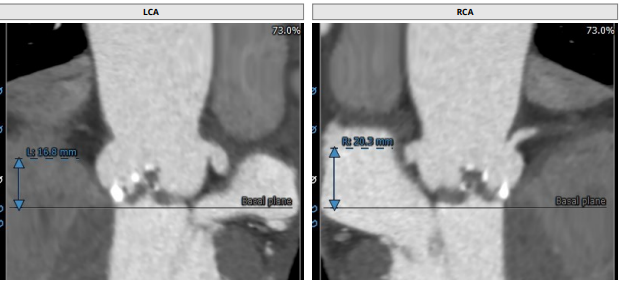

术前CT评估

入路分析:右股动脉

术前分析及手术策略

患者为Type0型二叶瓣,瓣叶明显增厚,中度钙化,法式窦结构不大,双冠高度可,初步判断冠脉风险低,升主动脉明显增宽,左室大小正常,主动脉弓部走行较平缓,推荐右侧股动脉为主入路。